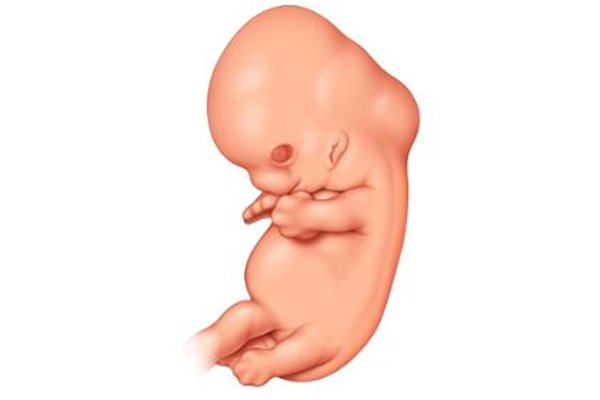

في الأسبوع الثامن من الحمل، ينمو طفلك بمعدل ملليمتر واحد في اليوم وتتشكل الشفاه والأنف والجفون، وعلى الرغم من أن الحمل قد لا يكون ظاهراً عليكِ، إلا أنك قد تلاحظين أن ملابسك أصبحت ضيقة بعض الشي.

طفلك الآن بحجم حبة الفاصوليا، يبلغ طوله 14 مم تقريباً، ويزن حوالي 2غم.

تستمرّ الأطراف بالاستطالة وتتكون الأصابع، ويتراوح طول الجنين في هذا الأسبوع ما بين 11-14 ملم، تتّضح وتظهر عيونه، وتتشكّل الشفة العليا والأنف، ويبدأ ظهره ورقبته بالاستقامة تدريجيّاً.

قلبُ طفلك ينبضُ الآن بمعدل (150- 170) نبض في الدقيقة، أي ما يعادل ضعف معدّل نبضات قلبكِ.

تطورٌ آخر جديد هذا الأسبوع، طفلكِ يقوم بحركات عفوية من الممكن أن تشعري بها.

يبدأ الجنين بالتحرك ابتداء من الأسبوع الثامن من الحمل، ولكن حركاته قد لا تشعرين بها وخاصة إذا كان هذا حملك الأول، ويتم الكشف عنها فقط بالتصوير بالموجات فوق الصوتية.